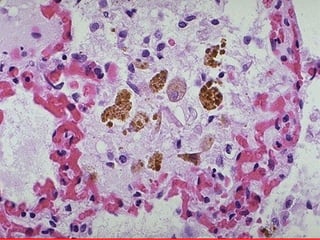

Acute Pulmonary Congestion

Heart Failure Cells” in Alveoli“

Chronic Pulmonary Congestion